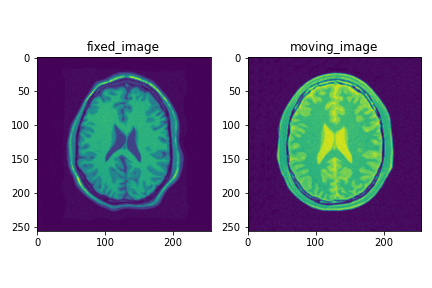

Data

githubに置かれている2次元CT脳画像を用います.3次元画像を扱う場合も同様の流れになります.

登録結果は以下のようになります.